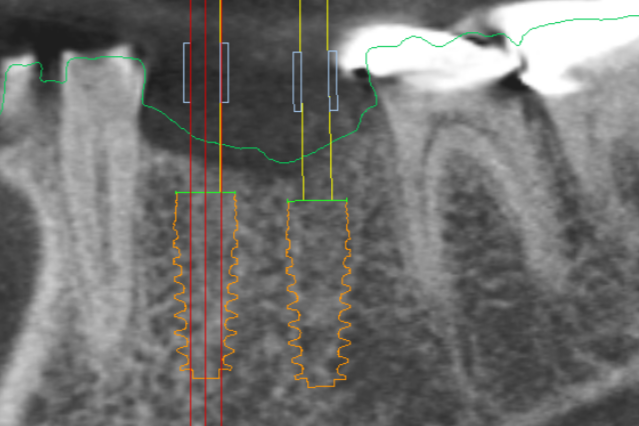

We offer state of the art 3-D x-ray imaging which allows a superior diagnostic level to 2-dimensional imaging. This imaging allows us to find pathology and plan implant cases with a level of precision beyond anything we could imagine 10 years ago.

Digital implant planning and the surgical guides they generate simplify the process